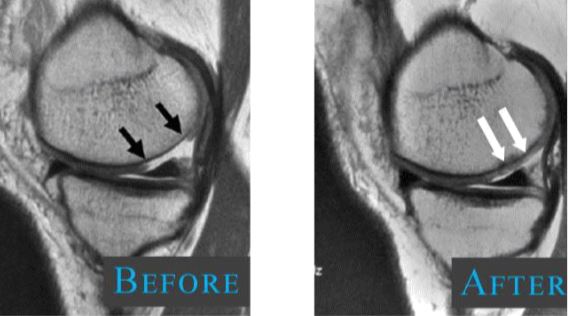

Knee Stem Cell Therapy is a recent advancement in knee pain and arthritis management. This approach to knee joint pain treatment has more advantages, when compared to the traditional approaches. This therapy extracts the stem cells, usually from an area of high density and then injects them into the damaged area to help the knee joint to heal naturally.

They can transform themselves to suit the environment, they are placed in. For instance, when stem cells are placed near a damaged cartilage, it can transform itself into a cartilage tissue later on.

The doctor will first numb the back of the hip and take a small bone-marrow stem cell sample through a needle. The harvested stem cells are then sent for processing and the patient will be asked to rest.

After the processing of the stem cells, the doctor will then re-inject the stem cells and natural growth factors from the patient’s blood platelets to the damaged area.